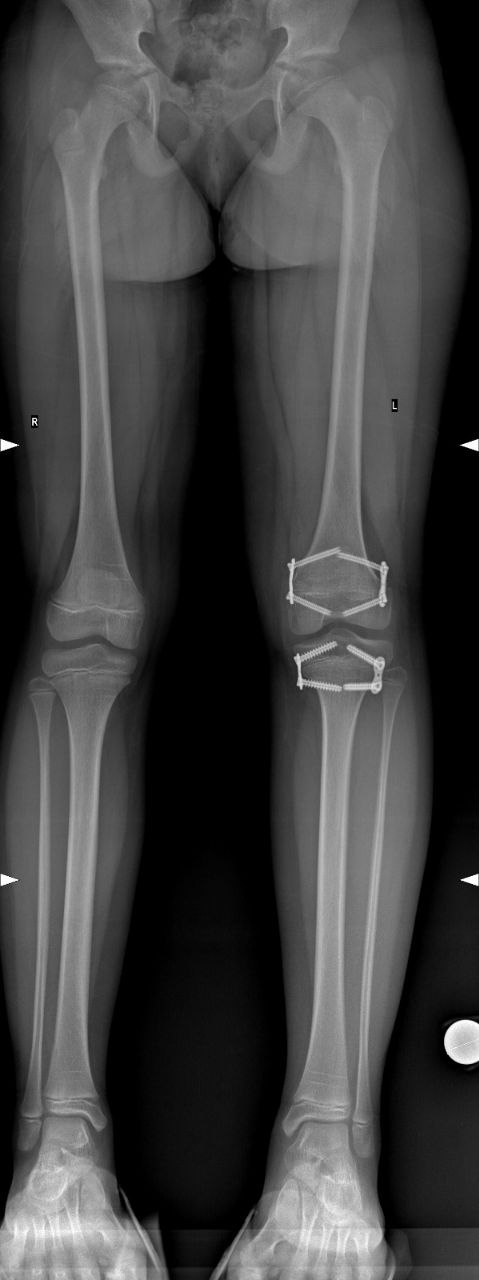

Девочка, 8 лет. Диагноз: Врожденное укорочение правой нижней конечности, 3,0 см. До операции и через год после операции, полная коррекция разновеликости